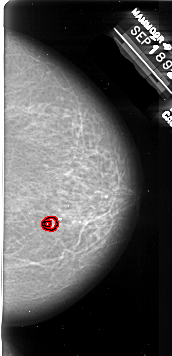

RIGHT_CC LINES 6406 PIXELS_PER_LINE 3091 BITS_PER_PIXEL 16 RESOLUTION 42 OVERLAY

FILE: A_1009_1.RIGHT_CC.OVERLAY

TOTAL_ABNORMALITIES 1

ABNORMALITY 1

LESION_TYPE MASS SHAPE IRREGULAR MARGINS SPICULATED

ASSESSMENT 4

SUBTLETY 1

PATHOLOGY MALIGNANT

TOTAL_OUTLINES 2

BOUNDARY

CORE